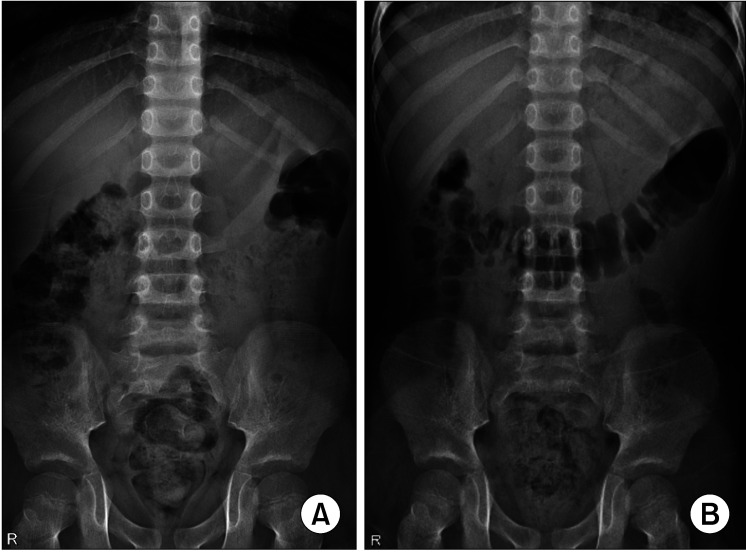

Materials and methods: Forty-five patients with lower urinary tract dysfunction (LUTD) received polyethylene glycol for 2 months before bladder medication for LUTD. Based on partial response to LUTD following treatment, we divided the patients into LUTD-fecal impaction (FI) and LUTD not attributed to FI (LUTD-NFI) groups. Pre/post-treatment kidney, ureter, and bladder (KUB) were compared with respect to several radiographic parameters. Items with significant changes after treatment were included in the scoring system. The accuracy and inter-rater agreement were also evaluated.

Results: Cecal dilation, descending colon dilation, fecal quality, and overall haziness were found to undergo significant changes after laxative treatment. We assigned 0 to 2 points for each item, with a total score of 8. Receiver operating characteristic curve analysis revealed a cutoff value of 5 between LUTD-FI and LUTD-NFI, with 79% sensitivity and 88% specificity. The scoring system was instructed to six doctors who were unaware of it and was then tested on previous patients, which showed a substantial concordance rate (κ=0.79, p<0.05).